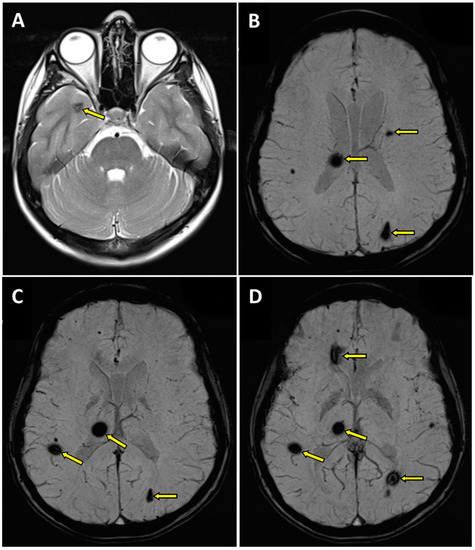

2. A Case Report

- -

- within the right thalamus (transverse dimensions of approx. 6 × 3.5 mm), with hemosiderin deposits,

- at the fronto-parietal junction on the right side in the subcortical location (transverse dimensions of approx. 3 × 5 mm),

- in the semioval center on the left side (transverse dimensions of approx. 7 × 4 mm),

- within the left occipital lobe (transverse dimensions of approx. 10 × 6 mm),

- in the right temporal lobe (transverse dimensions of approx. 7 × 3 mm and approx. 8 × 5 mm),

- in the area of the right frontal lobe (transverse dimensions of approx. 10 × 6 mm).